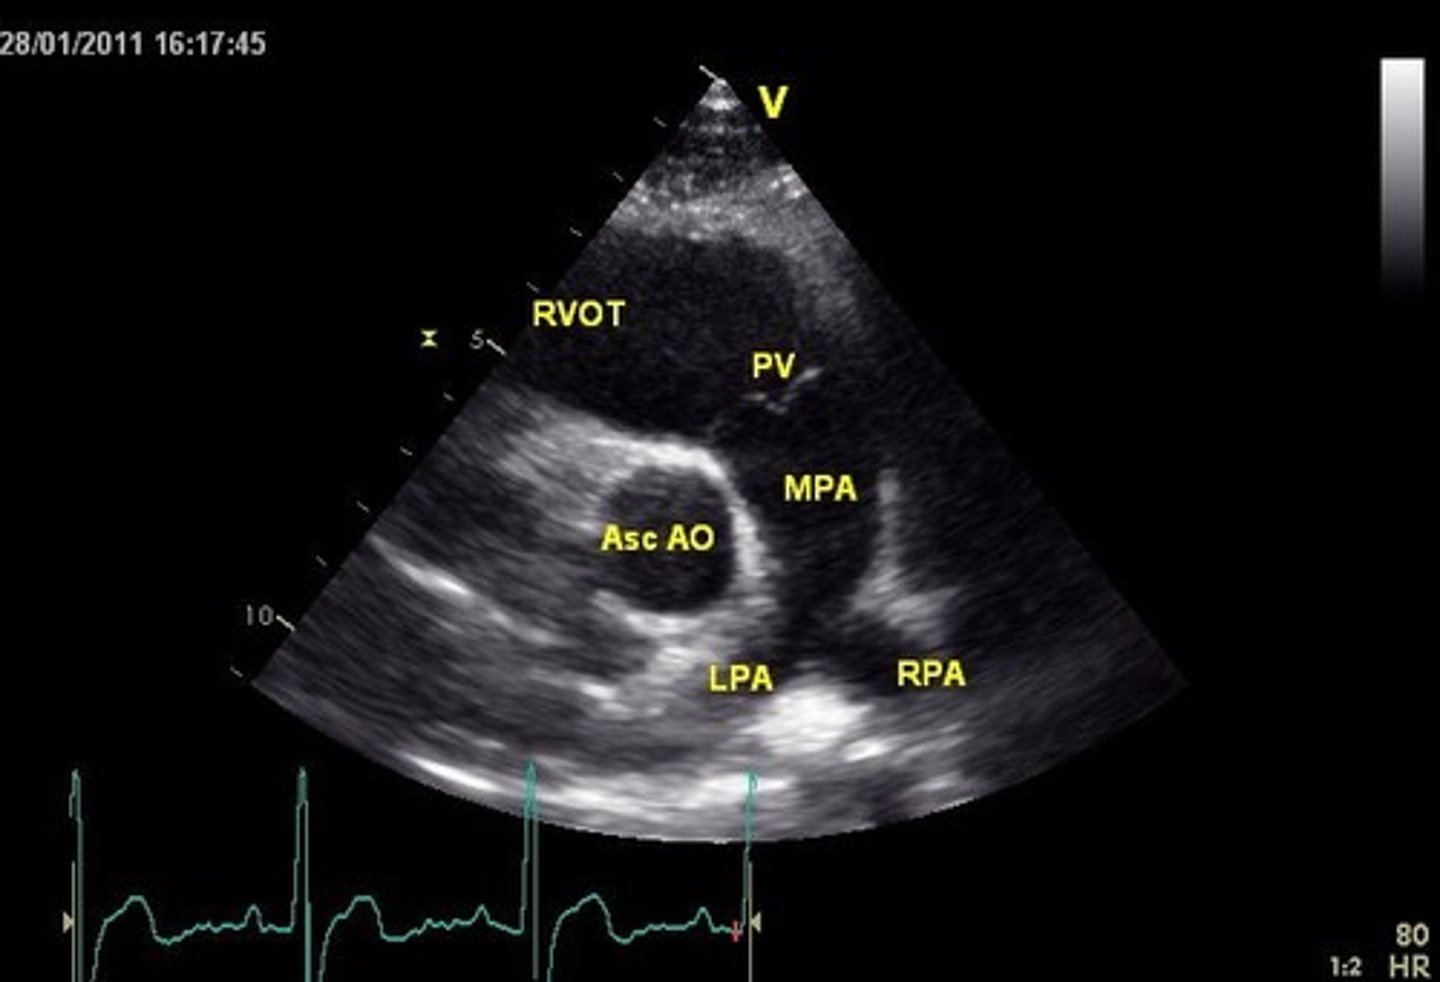

RVOT is used to visualize _______

PV

PSSA AoV is used to visualize _____, ____, and ___

TV, PV, AoV